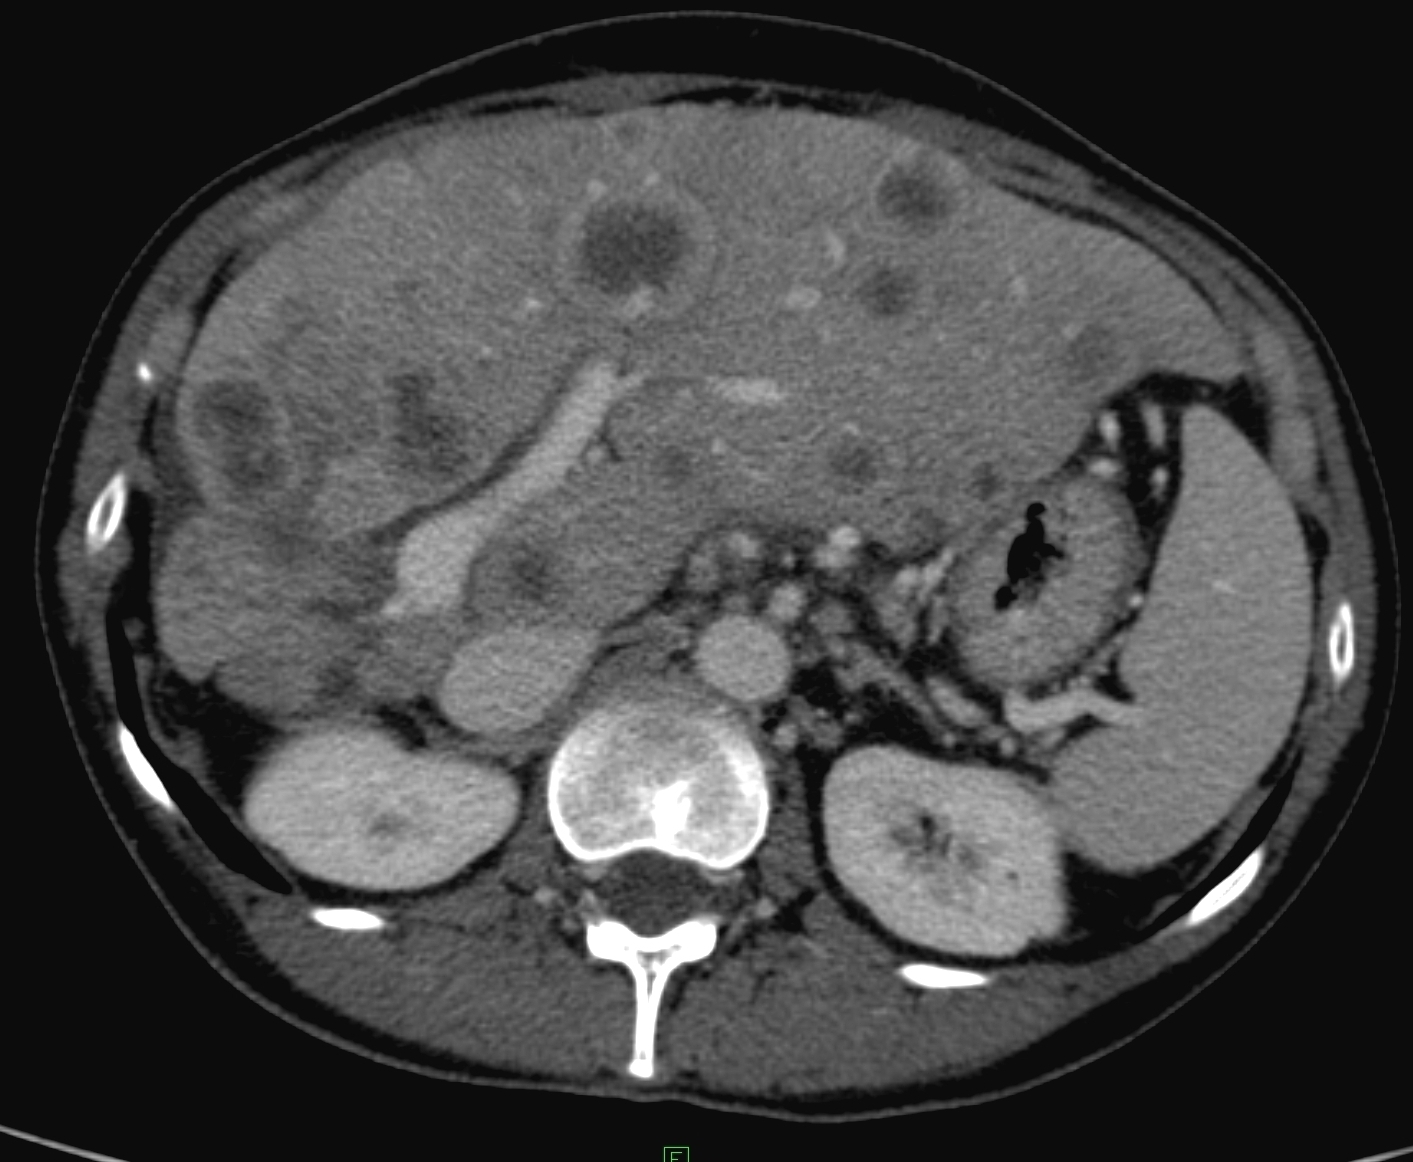

Breast cancer (Figure 23), pancreatic cancer, testicular cancer, ovarial cancer, malignant lymphoma, carcinoid, gastrointestinal adenocarcinoma.

Figure 23: Metastases of breast cancer in the liver, contrast enhanced CT